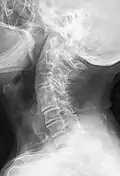

Block vertebrae of the cervical spine (vertebrae 4 and 5). Probably based on degenerative or inflammatory changes. -